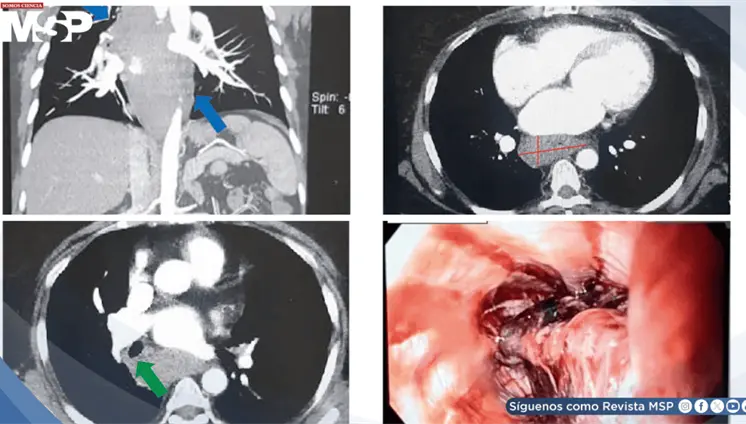

Paciente con marcapasos reciente desarrolló endocarditis infecciosa por Staphylococcus epidermidis complicada con pseudoaneurisma del intervalo mitral-aórtico y perforación valvular mitral.

La compresión de la arteria coronaria principal izquierda (LMCA) por dilatación de la arteria pulmonar representa una complicación subdiagnosticada de la hipertensión pulmonar severa, con prevalencia del 6%.

Un caso de ruptura de absceso amébico en la vena cava inferior, con un trombo que se extiende hasta la aurícula derecha y tromboembolismo pulmonar tratado con éxito.

Los médicos encontraron casi un litro de pus alrededor del corazón, confirmando una pericarditis purulenta que evolucionó a una forma constrictiva, impidiendo al corazón latir con normalidad.